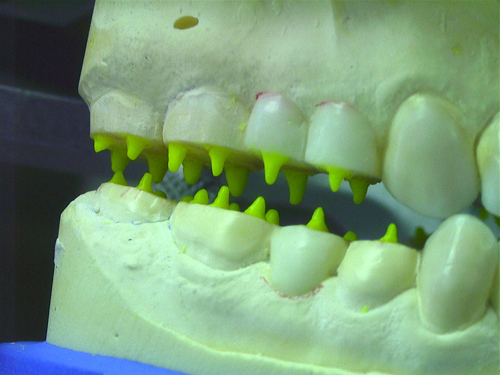

ABSTRACT El Bruxismo es una entidad patológica en la que concurren diferentes factores. Entre ellos el stress que conlleva consigo la vida moderna, constituye el Factor Predisponente sobre el que se ha abundado en innumerables tratamientos de tipo general, actuando sobre la psiquis y el comportamiento del individuo, ya sea con fármacos o bien mediante medios psicológicos. Sin embargo, como tantos desequilibrios provocados por el stress, confluyen siempre con un Factor Desencadenante, que en el caso del Bruxismo se encuentra en las desarmonías entre los componentes varios del Sistema Estomatognático. DESARROLLO Paciente varón, de 43 años, constitución atlética. A la inspección se observan desgastes oclusales que alcanzan la calidad de Facetas Parafuncionales, con dentina expuesta y empastes totalmente gastados y evidentes signos de falta de Disclusión Canina de ambos lados. Sobre dicho montaje se realiza un Encerado Progresivo de Diagnóstico, aportando en el mismo los elementos necesarios para obtener todos los principios básicos de una Oclusión Orgánica. FIG. 6 a 24 Una vez aprobado el fisiologismo de la oclusión en el articulador, se reproducen modelos de yeso con la nueva situación, y se estampa un SET UP en cada maxilar. FIG. 25/26 Procedemos entonces al tallado de las piezas correspondientes a la Guía Anterior, y rebasamos los estampados, creando en boca una nueva situación desoclusiva, que permanece en boca durante los pocos días que transcurren entre la primera y segunda visita de trabajo. FIG. 27/33 Ya abordando en esta segunda visita los sectores posteriores, tanto superiores como inferiores, tallamos siempre de manera supragingival, destacando la importancia vital de la forma obtenida en las provisionales, a las que abrimos plenamente las troneras para lograr una correcta higiene. FIG.34 a 43 FIG. 44 a 52 Efectuados los colados en oro y probados en boca, en el laboratorio se confecciona el bizcochado de la nueva Guía Anterior, la que puede o no copiarse de la Guía Anterior provisional, mediante la técnica denominada Trayectoria Funcionalmente Generada, que consiste en realizar en la platina del articulador un registro estereográfico sobre acrílico Duralay en polimerización. FIG. 57/58 Ajustados todos los detalles mediante esta técnica, se instala en boca en forma Provisional y se deja funcionando una semana o dos, al cabo de las cuales se chequean las disclusiones , los ajustes, la eficacia masticatoria, la carencia de sintomatología articular y muscular. FIG.59 a 63 PIE DE FOTO FIG.9 OBTENCIÓN DE LA GUÍA ANTERIOR FIG.10 Y 11 PITOMBOS. ALINEAC. TRIDIMENSIONAL FIG.12 PITOMBOS. DISCLUSIÓN DER. FIG.13 PITOMBOS. DISCLUSIÓN IZQ. FIG.14 WILSON INF. FIG.15 WILSON SUP. FIG.16 BOCA DE PEZ INF. FIG.17 BOCA DE PEZ SUP. FIG.18 VISTA OCLUSAL FIG.19 O.R.C. FIG.20 DISCLUSIÓN DERECHA FIG.21 CRESTAS TRIANG. INT. FIG.22 CRESTAS TRIANG. INT. FIG.23 CRESTAS TRIANG. INT. FIG 24 CRESTAS TRIANG. INT. FIG.59 DISCLUSIÓN IZQ. FIG.60 DISCLUSION IZQ. FIG.61 DISCLUSIÓN DER. FIG.62 DISCLUSION DER. FIG. 63 AJUSTE PERIFÉRICO